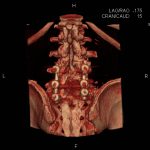

- Diagnosticul fracturilor:

- Unice

- Multiple

- Cu înfundare

- Complexe cranio-sinusale

- Complexe cranio-etmoidale

- Complexe cranio-orbitare

- Complexe cranio-faciale